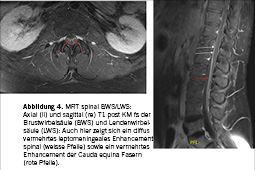

Bereits zu Beginn erfolgte eine Verlegung des Patienten auf die Intensiv- und Pflegestation wo der Patient im Verlauf eine zunehmende rechts- und proximalbetonte Tetraparese (Armabduktion rechts M2, Hüftbeuger M3, sonst M4-5) entwickelte, was bei erhaltenen bis lebhalten Reflexen im Rahmen einer Enzephalomyelitis interpretiert wurde. Der Allgemeinzustand des Patienten verschlechterte sich sodann erneut, wobei es im Verlauf passend zu einer Enzephalopathie zu einer Vigilanzminderung mit Benommenheit und zu einer Dysarthrie sowie Dysphagie kam, weshalb eine Intubation sowie später eine Tracheotomie erforderlich wurden. Erschwerend kam ein Harnwegsinfekt dazu, welcher den erneuten Einsatz von Antibiotika (Piperacillin/Tazobactam) während einer Woche erforderlich machte. Nach Auftreten eines generalisierten tonisch-klonischen Anfalls zeigte eine durchgeführte Bildgebung mittels CT des Neurocraniums keine neuen Aspekte. Ein ergänzende Magnetresonanztomografie (MRT) long spine zeigte den Befund einer spinalen Leptomeningitis sowie einer Polyradiukulitis (Abbildung 3 und 4). Ebenfalls bestand eine motorische Unruhe im Sinne einer Akathisie. Es erfolgte eine weiterführende symptomatische sowie supportive Therapie, worunter es zu einer Besserung der Beschwerden kam. Nach 4 Wochen, während denen der Patient 18 Tage IPS-pflichtig war, konnte dieser in stabilem Allgemeinzustand in die Rehabilitation entlassen werden. Während den 8 Wochen der stationären Rehabilitation wurde die initial noch bestehende Dysphagie mittels Logopädie deutlich verbessert. Obwohl ein selbständiges Gehen ohne Hilfsmittel nach Absolvierung der Rehabilitation wieder möglich war, persistierten eine verminderte Schritthöhe sowie fehlende Schutzschritte. Motorisch bestand zudem weiter eine starke Einschränkung der Abduktion des rechten Armes – ein Aufstehen vom Boden ohne Hilfsmittel war zudem weiterhin nicht möglich.